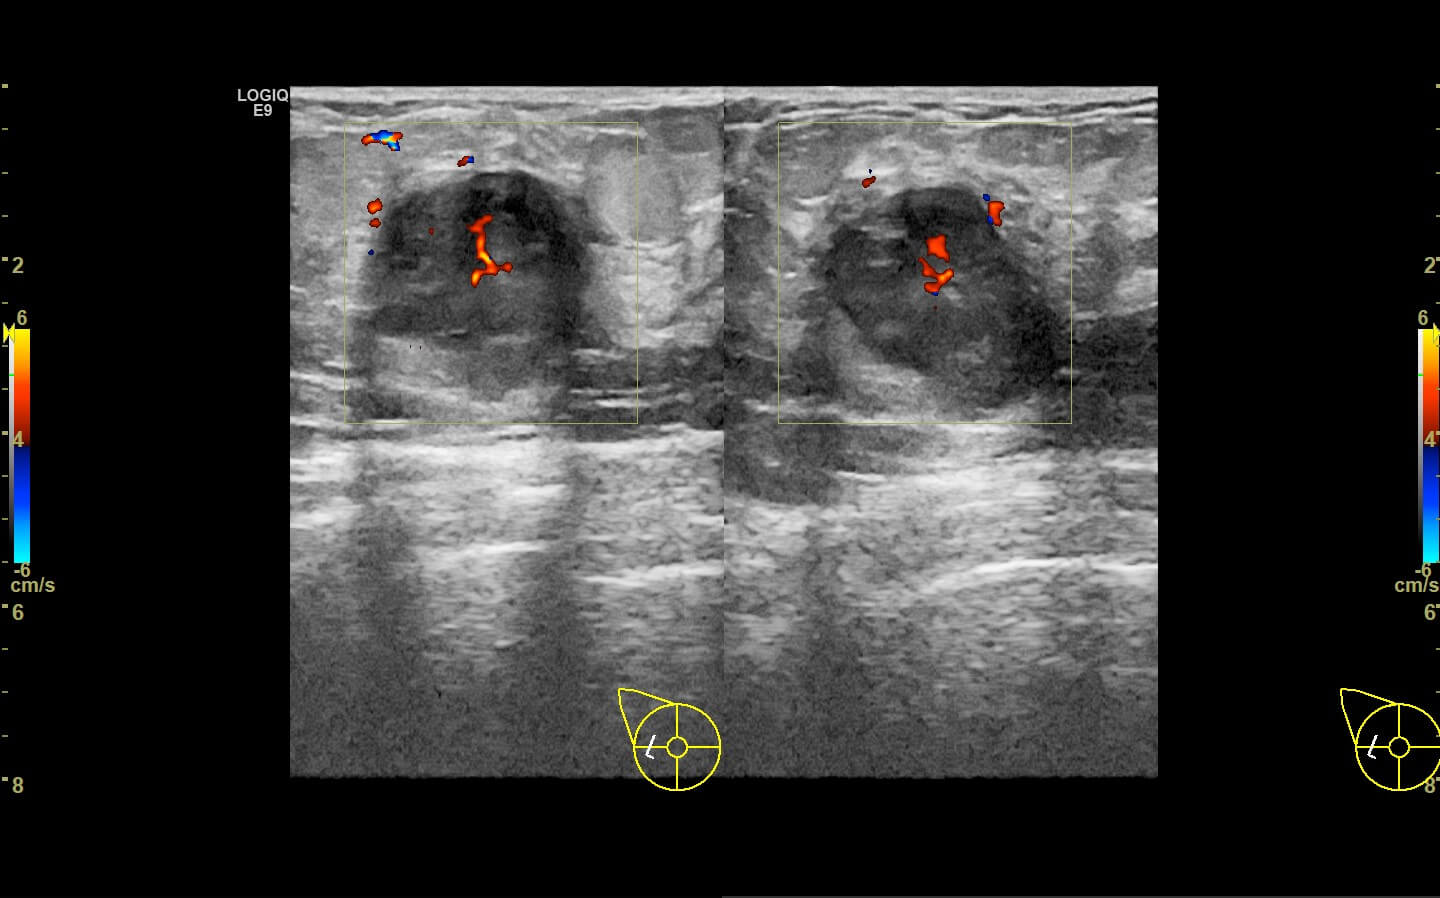

Mammogram revealed the presence of an irregular high density mass in the posterior third of the upper outer quadrant of the right breast with indistinct margins on two-dimensional mammogram. No internal calcification seen. No overlying skin thickening or retraction noted. DBT (Digital breast tomosynthesis) revealed the mass having spiculated margins and irregular shape. Corroborative ultrasound showed an irregular, heteroechoic solid mass at 10-11 O’clock position with anti-parallel orientation, microlobulated margins, posterior enhancement and internal necrotic/ cystic areas within. Mild internal vascularity was seen on color Doppler. No dilated ducts or intraductal extension was seen. No suspicious lymph nodes were present Further recommendation: Ultrasound guided core-needle biopsy with immunohistochemical analysis Management received: Right side lumpectomy with MRM Final histopathology: Metaplastic carcinoma (carcinosarcoma) with no nodal metastasis